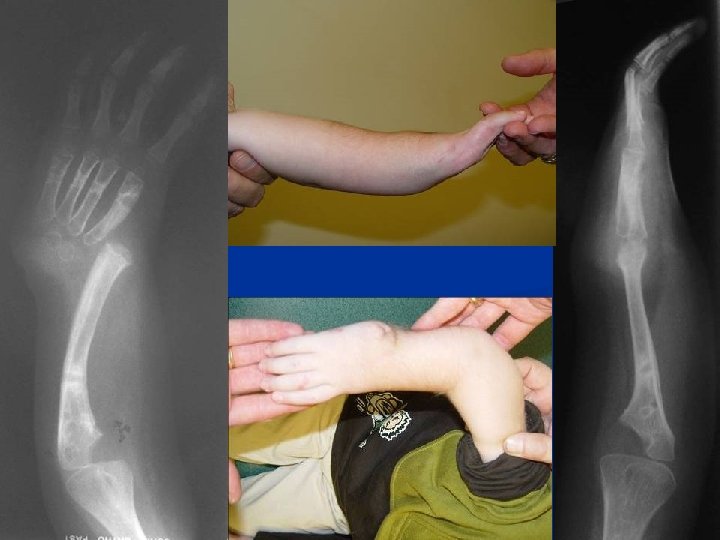

Ulnarization of the Carpus with Tendon Transfer of FCU

RCH: Poor Grip Strength Due to lack of fulcrum n Forearm shortening affects muscle length curve (Blick’s) n Excessive palmar flexion pull: dorsi flexion of hand increases grip strength n

Ulnarization n Converts head of ulna into a fulcrum due to radial pull of muscles fulcrum Muscle pull

Flexor Carpi Ulnaris Transfer • FCU is the major deforming flexor force • Transfer to dorsum converts it to a correction force • This helps improve finger flexion ROM and strength

Ulnarization vs Radialization n n n Paley (1998) Name describes direction of carpal translocation Volar approach Visualize all the N-V structures Transfer FCU tendon Extensile for elbow contracture release n n n Buck-Gramko (1979) Name describes change of ulna to a radius Dorsal approach Cannot visualize N-V structures Transfer FCR* *FCR usually absent

8 year followup

7 yr. followup radiographs

Ulnarization: Results 15 patients; 21 hands n Followup 1 -7 years n Recurrence: 0 n Growth arrest: 0 n

Ulnarization: Complications n 2 skin necrosis treated by debridement and secondary closure

Wrist Dorsiflexion PASSIVE preop -15° postop +36° ACTIVE postop 9°(10 -20°)

Preop: 79 mm (40 -175 mm) Postop: 102 mm (58 -188 mm) No Growth Inhibition